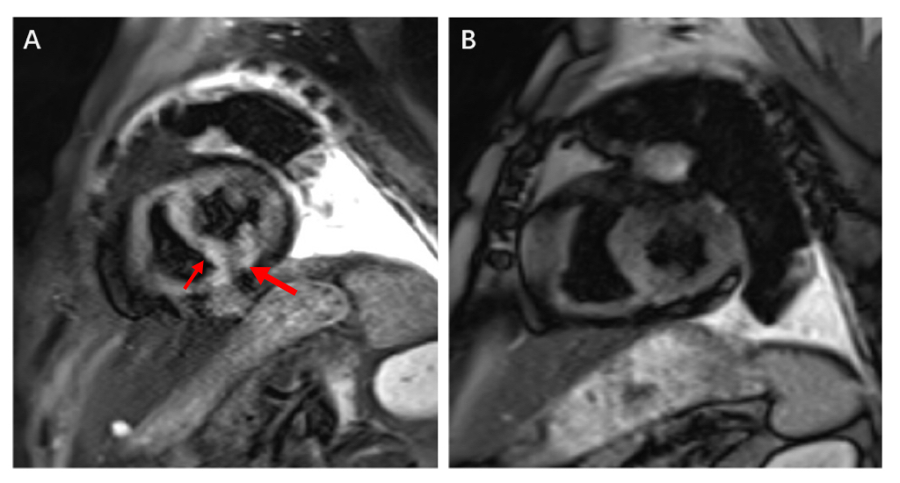

先处理心脏?传统冠脉支架植入后,需要服用抗血小板治疗至少3个月,等待意味着肿瘤进展、转移的风险与日俱增。先切肿瘤?麻醉和手术中心脏随时可能“罢工”,患者有生命危险!面对这一难题,胸科医院心内科、胸外科、麻醉科专家进行了多学科会诊,最终决定采用药物球囊血管扩张成形术进行救治。在解决心脏问题后,经过快速休养的王老伯又顺利接受了肺部肿瘤切除术。最近,他来医院复查显示,肺和心脏的状况都很好。

心内科副主任韩文正表示,“胸部肿瘤与心血管疾病具有共同的危险因素,对于这类围术期心血管高危的患者,心功能评估与监测十分重要,既能降低心血管疾病风险,也是为外科手术或后续治疗安全保驾护航。”

图A 冠脉造影术提示血管高度狭窄。图B 药物球囊扩张术后复查狭窄解除。图C 日前复查显示未见明显再狭窄